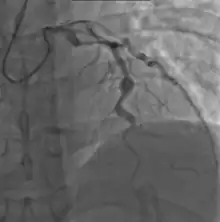

Angiography showing ectatic LAD, with largest aneurysm = 6.5 mm in diameter

Heart complications are the most important aspect of Kawasaki disease, which is the leading cause of heart disease acquired in childhood in the United States and Japan.[31] In developed nations, it appears to have replaced acute rheumatic fever as the most common cause of acquired heart disease in children.[15] Coronary artery aneurysms occur as a sequela of the vasculitis in 20–25% of untreated children.[52] It is first detected at a mean of 10 days of illness and the peak frequency of coronary artery dilation or aneurysms occurs within four weeks of onset.[48] Aneurysms are classified into small (internal diameter of vessel wall <5 mm), medium (diameter ranging from 5–8 mm), and giant (diameter > 8 mm).[31] Saccular and fusiform aneurysms usually develop between 18 and 25 days after the onset of illness.[15]